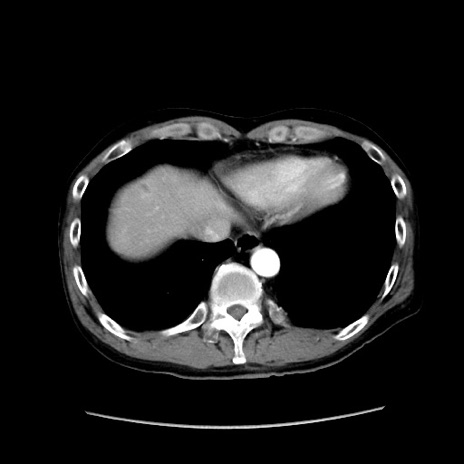

症例37(横断像)

【症例】40歳代 男性

【主訴】腹痛

【現病歴】4時間ほど前に電車に乗車中に臍部上より腹痛出現。徐々に増悪し起立困難となり、救急外来受診。生ものは数日食べていない。今朝お雑煮を食べた。

【身体所見】BT 36.8℃、BP 117/84mmHg、HR 91/min、SpO2 97%、苦悶様、腹部:臍上部広範囲圧痛あり、反跳痛±

【データ】WBC 8100、CRP 0.03